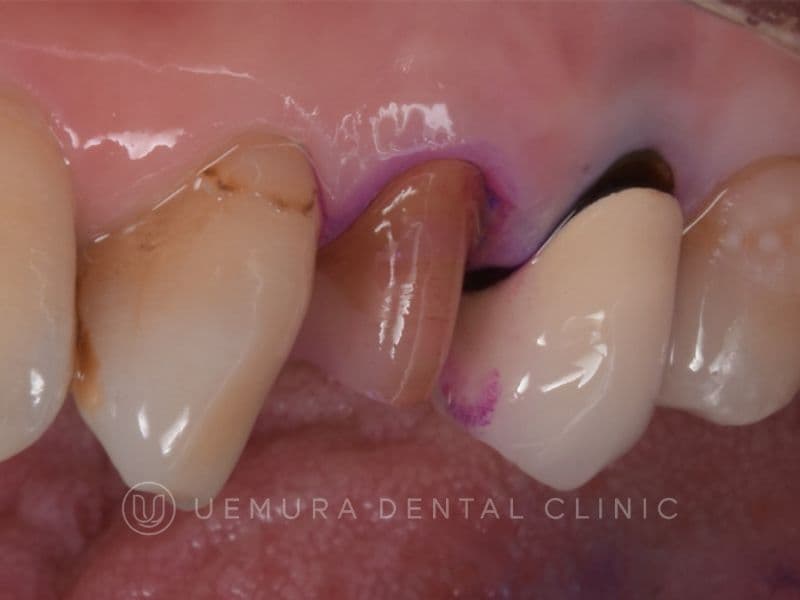

適合が悪く歯茎が腫れてしまった症例

| 主訴 | 前歯を綺麗にしたい |

|---|---|

| 診断名 | 不適合修復物、う蝕、歯肉炎 |

| 年齢・性別 | 22歳・女性 |

| 治療期間・回数 | 3回 |

| 治療方法 | CRによるダイレクトベニア |

| 費用 | ¥88,000×4本 |

| デメリット・注意点 | 噛み合わせの状態によっては欠ける場合があります。 ナイトガードの使用をおすすめします。 |

| 備考 | 古い詰め物が合ってない(適合が悪い)ため、歯肉炎になっている状態でした。詰め物の精度が悪く、フロスも通らない状態なので、どんなに頑張って磨いても歯肉炎が治ることはありません。 治療は患者様と相談の上、3回に分けました。小分けにした方が歯の形もしっかり作れますし、色がちゃんと合っているのか確認もできます。 3回目の治療時に最終の仕上げ・研磨を行いました。 治療前と治療後の歯肉の状態が違うのがお分かり頂けると思います。 適合の良い詰め物・被せ物=清掃しやすい環境に整っているので、虫歯や歯周病の予防にも繋がり、結果的に歯が長持ちすることにも繋がります。 |